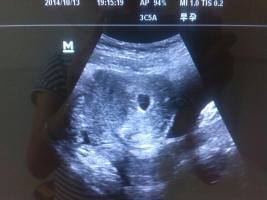

谁能帮忙看B超图片,以下是孕40天与孕13周照的B超图,现在是二胎压力大啊,请帮忙看看吧 点击展开 匿名用户 2014-12-08 10:29 为您推荐: 其他回答 从B超单子上是看不出男女的,只有在B超的照射下才能看到生殖器官,才能分辨出男女。 ok天秤座10 2014-12-08 21:03 相关问题 为什么23周照的彩超没有彩色图片呢,而是和刚怀孕的时候照的B超一样子是一张A4纸打印出来的呢! 什么样B超图长形和圆形怀孕图片 怀孕64天了,是二胎,做了二次B超,54天和61天时做的,只发现胎芽,却没有心管搏动,也没见红的